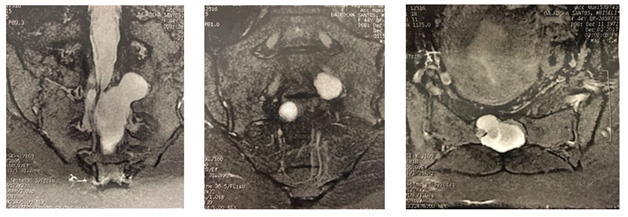

Computed tomography: Significant bone destruction of posterior elements of S1 and S2 (Figure 1).

Figure 1 CT showed important destruction of posterior elements of: A. S1 and B. S2.